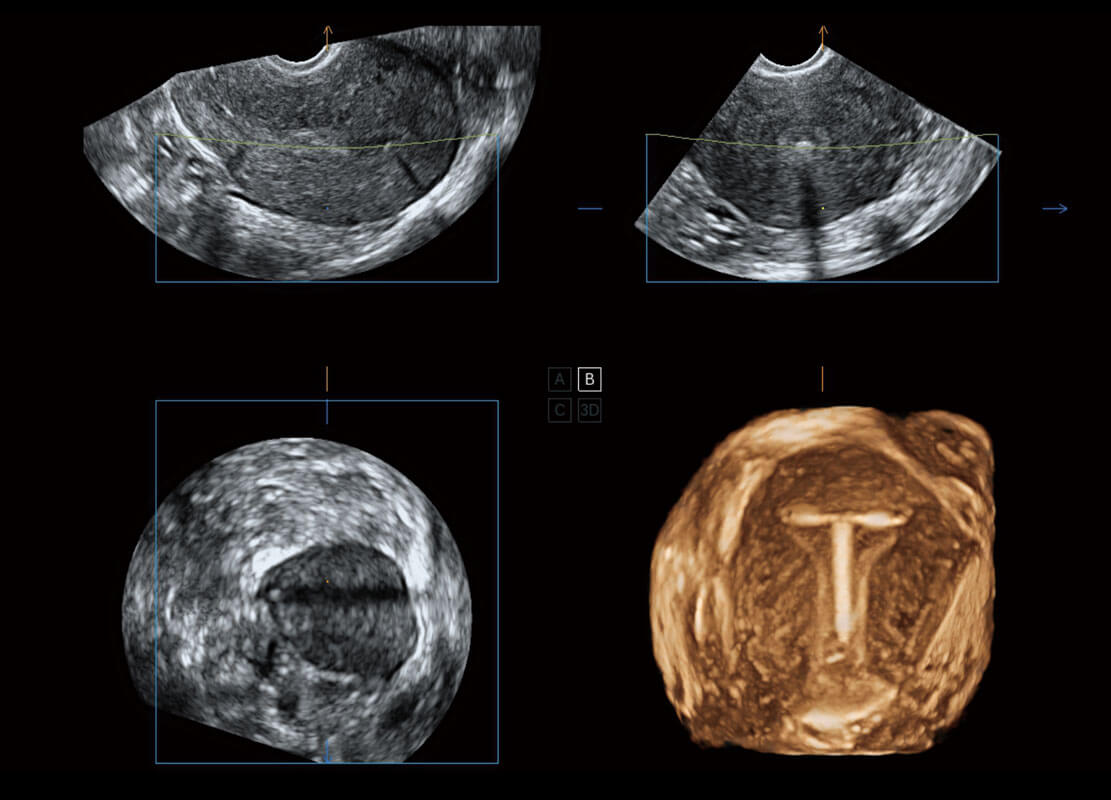

盆底超声

P60为盆底超声检查提供应用方案,多种腔内及腹部容积探头提供从二维、三维到四维的优异图像品质,实时快速三维容积数据获取,专业的测量工具包等人性化设计,为超声医生诊断提供有力保障。

S-Pelvic

能够简化盆底检查的操作流程,可在二维模式及三维成像模式下实现一键自动提取出标准切面、自动识别当前切面、自动测量,提升盆底检查的高效性,同时也能让青年医生快捷的获得准确的检查结果。